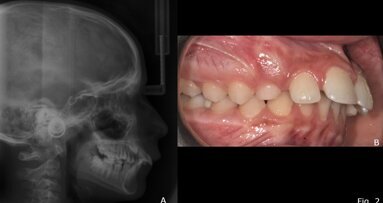

Le malocclusioni scheletriche di II classe sono causate dalla retrusione mandibolare in circa l’80% dei casi totali, il che ha spinto molti clinici e ...